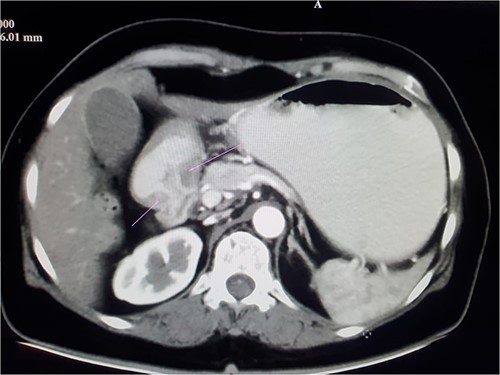

A 48-year-old female who was previously healthy presented with recurrent episodes of vomiting, loss of appetite and loss of weight for 1 month duration. On clinical examination, she was emaciated with a body mass index of 17, not icteric, a vague mass felt over the right hypochondriac region. She was haemodynamically stable. Initial evaluation with gastroscopy showed growth at the pyloric antrum causing gastric outflow obstruction. Biopsy revealed poorly differentiated adenocarcinoma. Contrast enhanced computed tomography (CECT) of the chest abdomen and pelvis showed mucosal thickening seen in the distal lesser curvature, adjacent antrum and pylorus with contrast enhancement suggestive of stomach neoplasm involving pylorus with few tiny regional lymphadenopathies and no distant metastasis (Fig. 1).